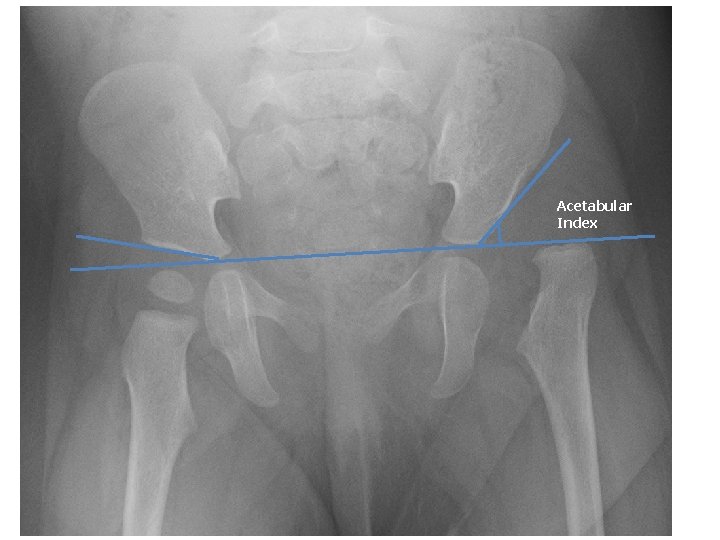

Acetabular Index